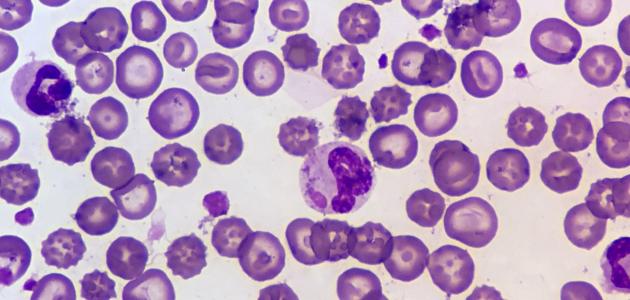

يعتمد تشخيص تليف الكبد على تقييم حالة المريض وإجراء عدة فحوصات، ومنها:

- تقييم الطبيب: حيث يطرح الطبيب أسئلة لتحديد العوامل المسببة.

- تحاليل الدم: خاصة تلك المتعلقة بوظائف الكبد.

- فحوصات تصويرية: مثل التصوير بالموجات فوق الصوتية والرنين المغناطيسي.